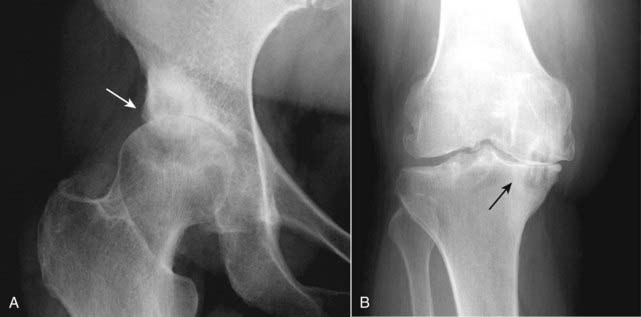

Figure 23-5 Osteoarthritis of hip (A) and knee (B).

In osteoarthritis, destruction of the cartilaginous buffer between the apposing bones of a joint leads to narrowing of the joint space most often on the weight-bearing side of the joint. In the hip (A), the superior and lateral surface is most affected (solid white arrow) while in the knee (B), the medial compartment is more affected (solid black arrow).